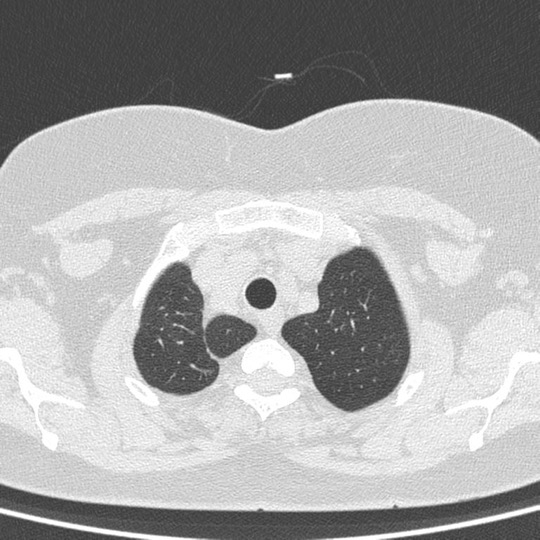

An Azygos lobe fissure is seen on right side. It extends from the lateral aspect of the vertebral body posteriorly, to the right brachiocephalicvein and SVC anteriorly.